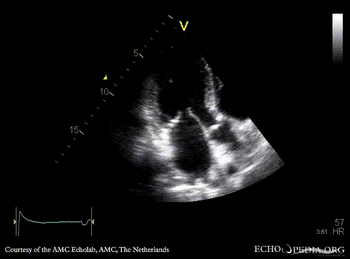

A4CH: normal systolic function of left ventricle A2CH